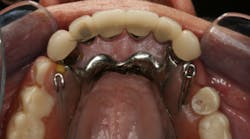

This clinical case began with a frustrated 75-year-old patient, who, after many years of failed attempts to repair the functional problem, came to the realization that a different solution was in order. The existing problem of an upper removable precision attachment partial denture was addressed first. The issue at hand was that the partial denture was perforated at the precision attachments, with the upper left side being more significant compared to the right side (figures 1–5). As a result, retention was adequate on the right side, but limited on the left. The patient was also concerned about esthetics, but needed a solution that kept a restricted budget in mind.

Occlusion: Localized wear noted on the lower anterior teeth, especially on teeth Nos. 22 and 23. Upper and lower planes of occlusion are not compatible for ideal function and esthetics.

Dentition: Upper anterior splinted crowns had open margins and caries. Radiographs confirm decay, along with open margins (figures 6–11). Lower incisal anterior wear noted (figure 2).